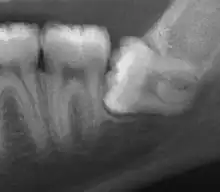

Impacted wisdom tooth with a horizontal orientation

An ectopic tooth, also known as an impacted tooth, is a tooth that develops in an abnormal position and fails to erupt into its normal location in the oral cavity. [1] [2] Ectopic teeth can cause a variety of symptoms, such as pain, swelling, and infection, and they can lead to more serious complications if left untreated.

This condition can affect both deciduous teeth and permanent teeth, although it is more common in the permanent teeth.

Diagnosis of ectopic teeth typically involves a comprehensive dental examination, including X-rays and other imaging tests. Treatment options for ectopic teeth depend on the location and severity of the condition, as well as the age and overall health of the patient. In some cases, observation and monitoring may be sufficient, while in other cases, surgical intervention may be necessary to remove the ectopic tooth and prevent further complications.[5]